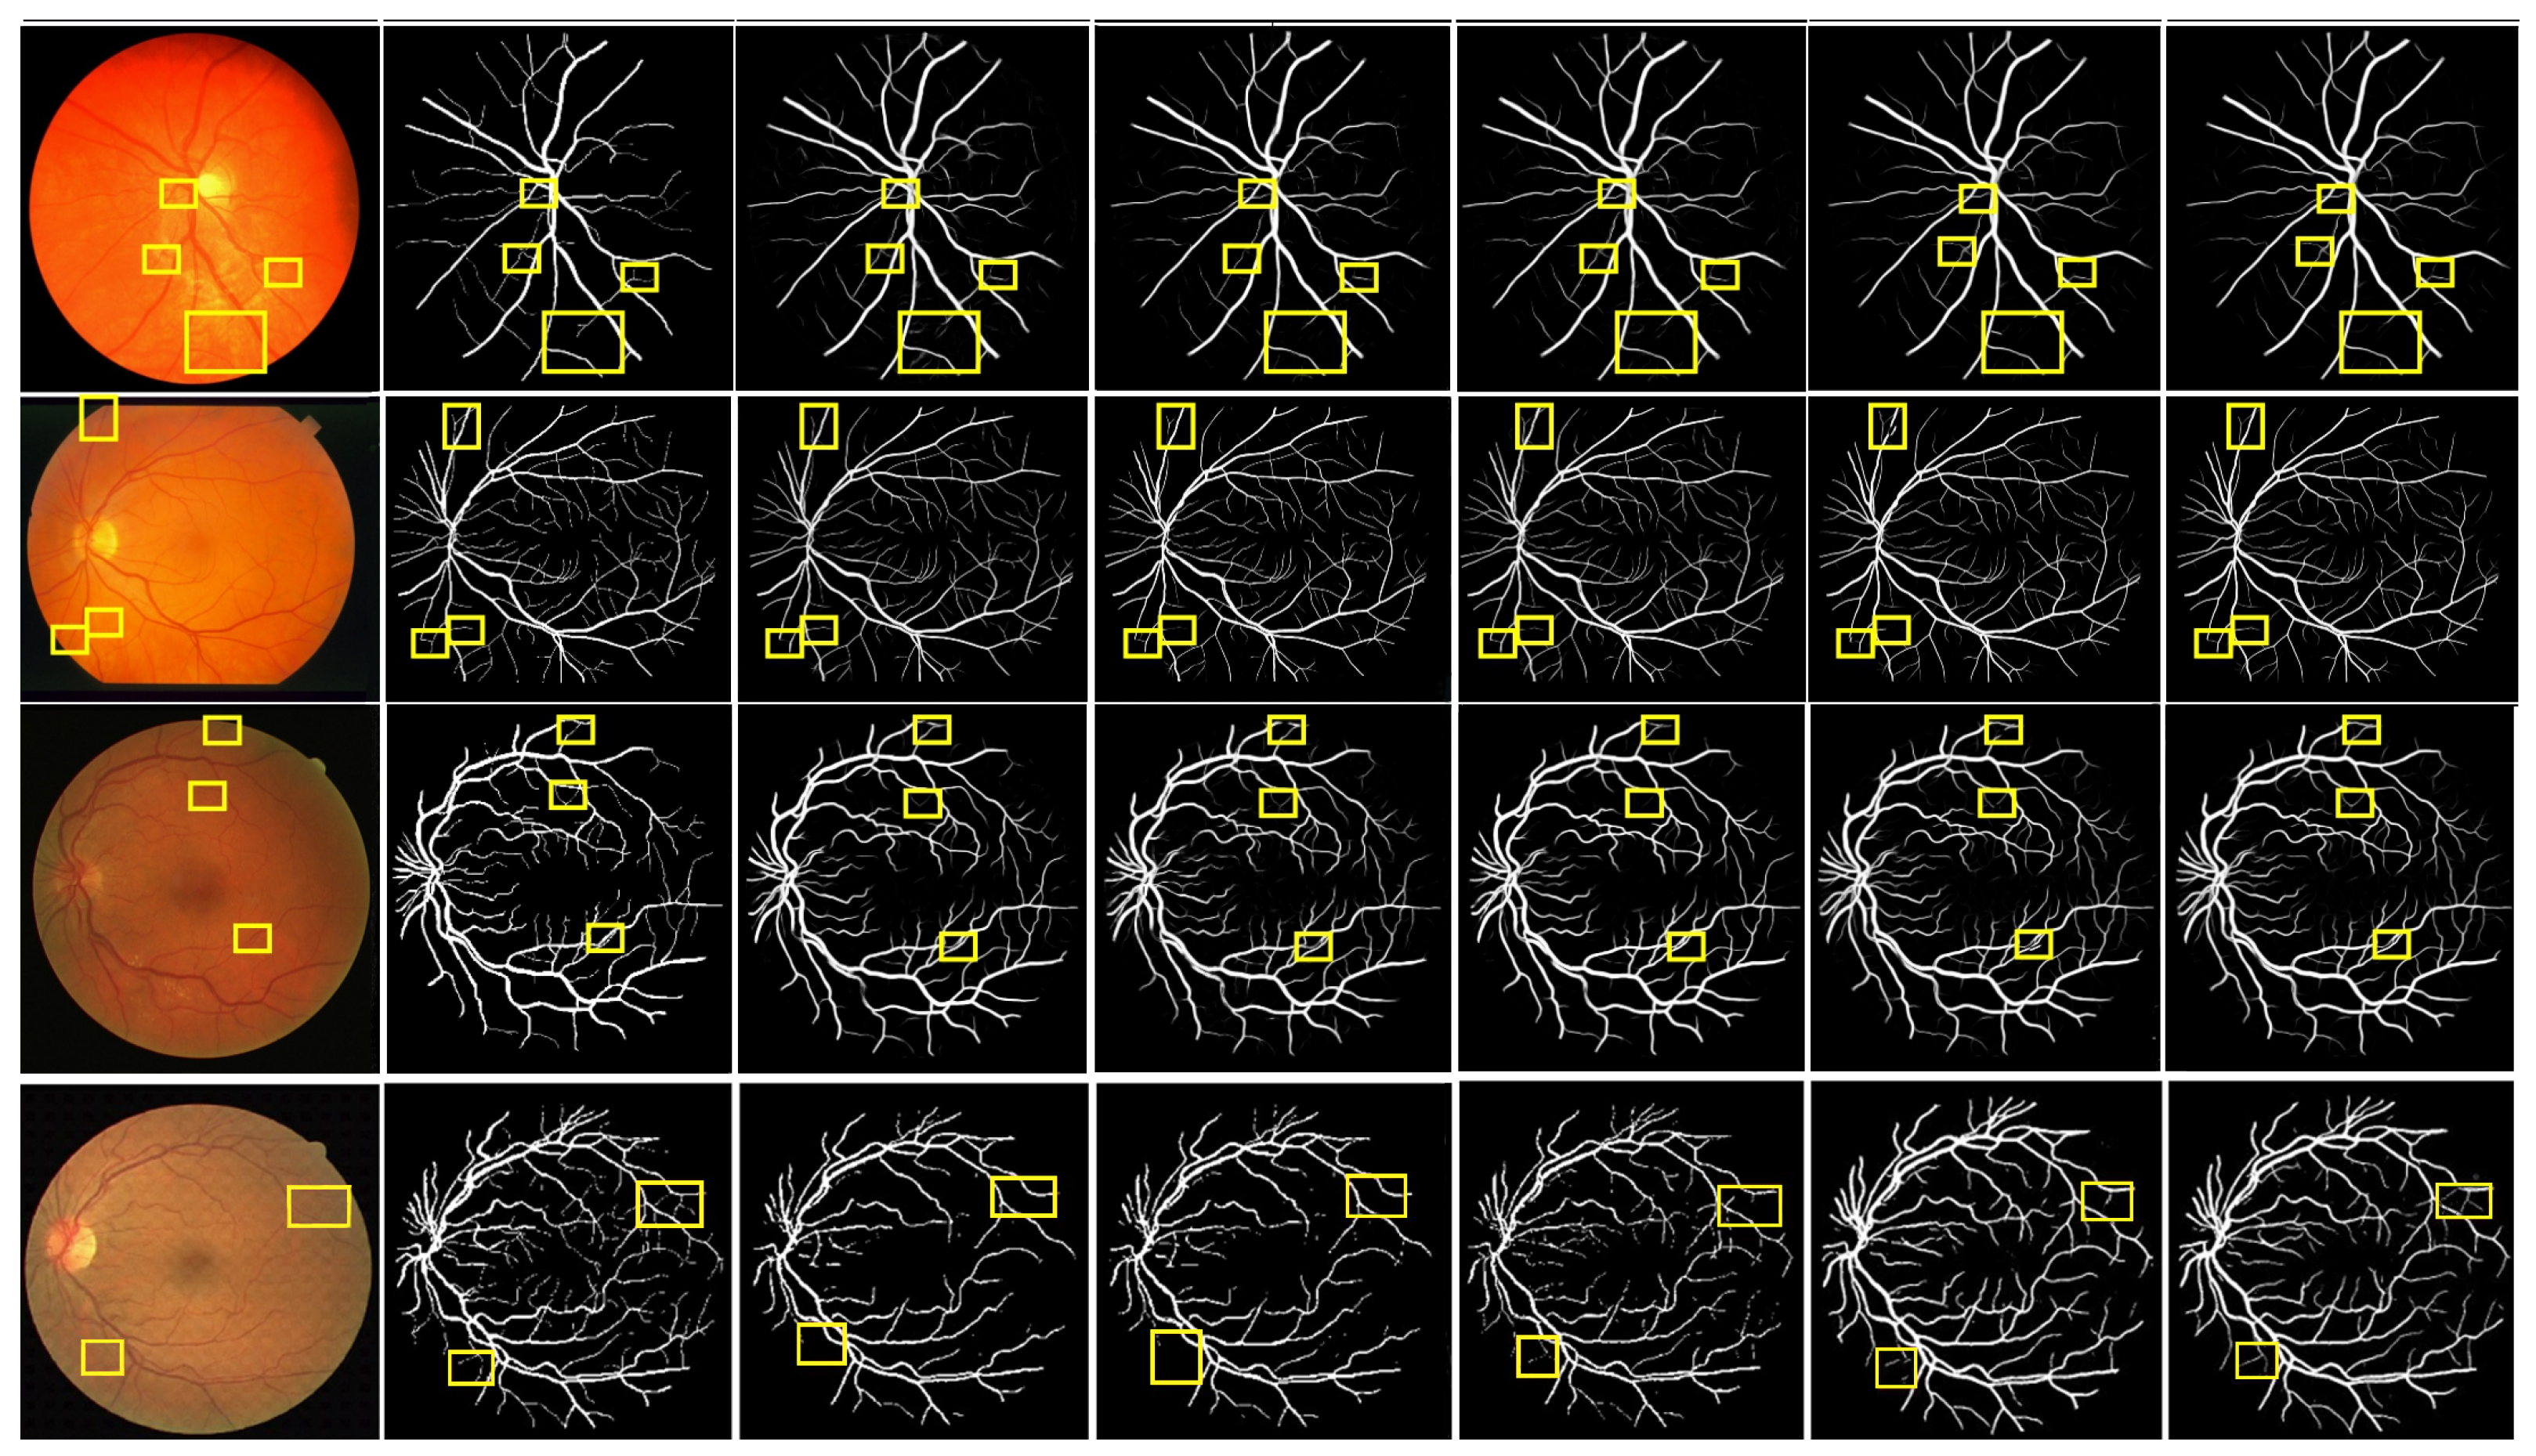

4.8. Ablation Study

To further validate the effectiveness of each module in the proposed algorithm, ablation experiments were conducted on the DRIVE and CHASE_DB1 datasets. The experimental results are presented in Table 6, and they reveal that M1 has already achieved commendable accuracy in RVS, though there remains potential for enhancement.

M2 demonstrated improvements across various metrics compared to M1, indicating that the WRM contributes to increased segmentation precision. Subsequently, M3 exhibited further enhancement over M2, suggesting that the GAM effectively extracts multi-scale vessel information. Additionally, M4 showed a notable improvement in all metrics compared to M3, highlighting that the GAM module mitigates the impact of background noise by integrating encoded information from different levels, thereby achieving a high-precision segmentation of small vessels. The aforementioned results substantiate the effectiveness and rationality of the MPCCN framework. The progressive performance improvements from M1 to M4 indicate the efficacy of the proposed modules in enhancing the U-Net algorithm. Notably, M4 achieved the highest AUC value, signifying that MPCCN excels in RVS. It accurately delineated both primary and small vessels while maintaining the connectivity of segmented vessels.

Furthermore, Figure 12 presents a qualitative comparison of the segmentation results produced by different modules within MPCCN. Each segmented image included two enlarged local detail views, allowing for a closer examination of specific areas. The segmentation performance of the individual modules in MPCCN varied, particularly when one or two modules were combined to evaluate their effect on the network’s overall performance. Notably, the combined use of all modules yielded significantly better results compared to any individual module, especially in the segmentation of microvessels. This demonstrates that the integration of multiple components enhances the network’s ability to capture fine details. In conclusion, MPCCN was proven to be a robust and highly accurate algorithm for RVS.